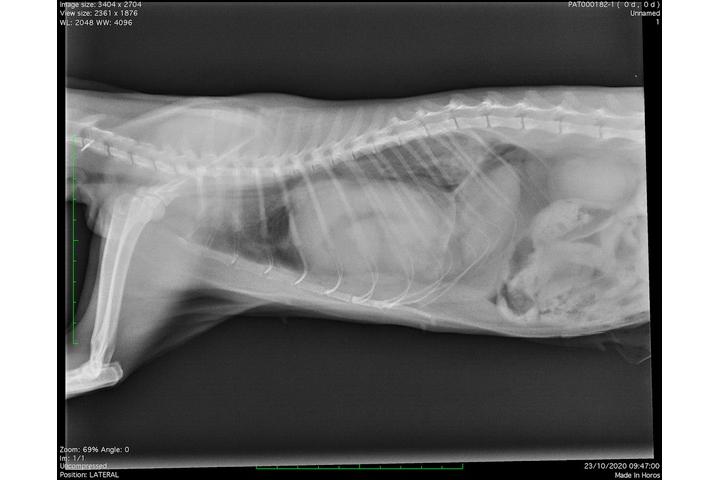

Suite à une hernie congénitale du diaphragme lui comprimant coeur et poumons , Michka doit subir une intervention délicate et couteuse : plus de 1500 euros . Merci de l aider